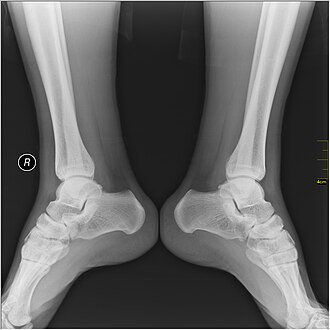

Gležanj, čičak, članak, (lat. malleolus) je lateralna i medijalna izbočina/nastavak na distalnom kraju kostiju potkoljenice.[1]

Ozljede u području gležnja česte su u sportaša, posebno u nogometu te su različite jačine (inteziteta) ozljede: od istegnuća do loma (frakture).